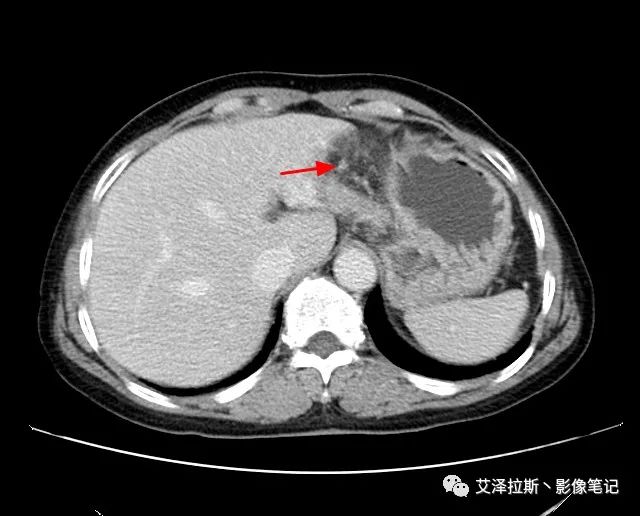

以下為累及的區域淋巴結,共計15個區域:

【影像所見】 胃竇部狹窄,胃壁環形增厚,小彎側見一巨大潰瘍,周圍伴“環堤征”,漿膜面不完整,胃周脂肪見網格狀條索影,病灶與肝臟左葉、胰腺鉤突脂肪間隙消失,增強掃描病灶明顯強化。引流區內約15個區域淋巴結受累。

【診斷意見】 胃竇部胃癌(T4N3期) 該病例腫塊突破漿膜層,與肝臟左葉、胰腺鉤突分界不清,脂肪界面消失,定為T4期; 受累及的淋巴結為15個區域,定為N3; 有無遠處轉移尚不明確,所以M期暫時無法確定。